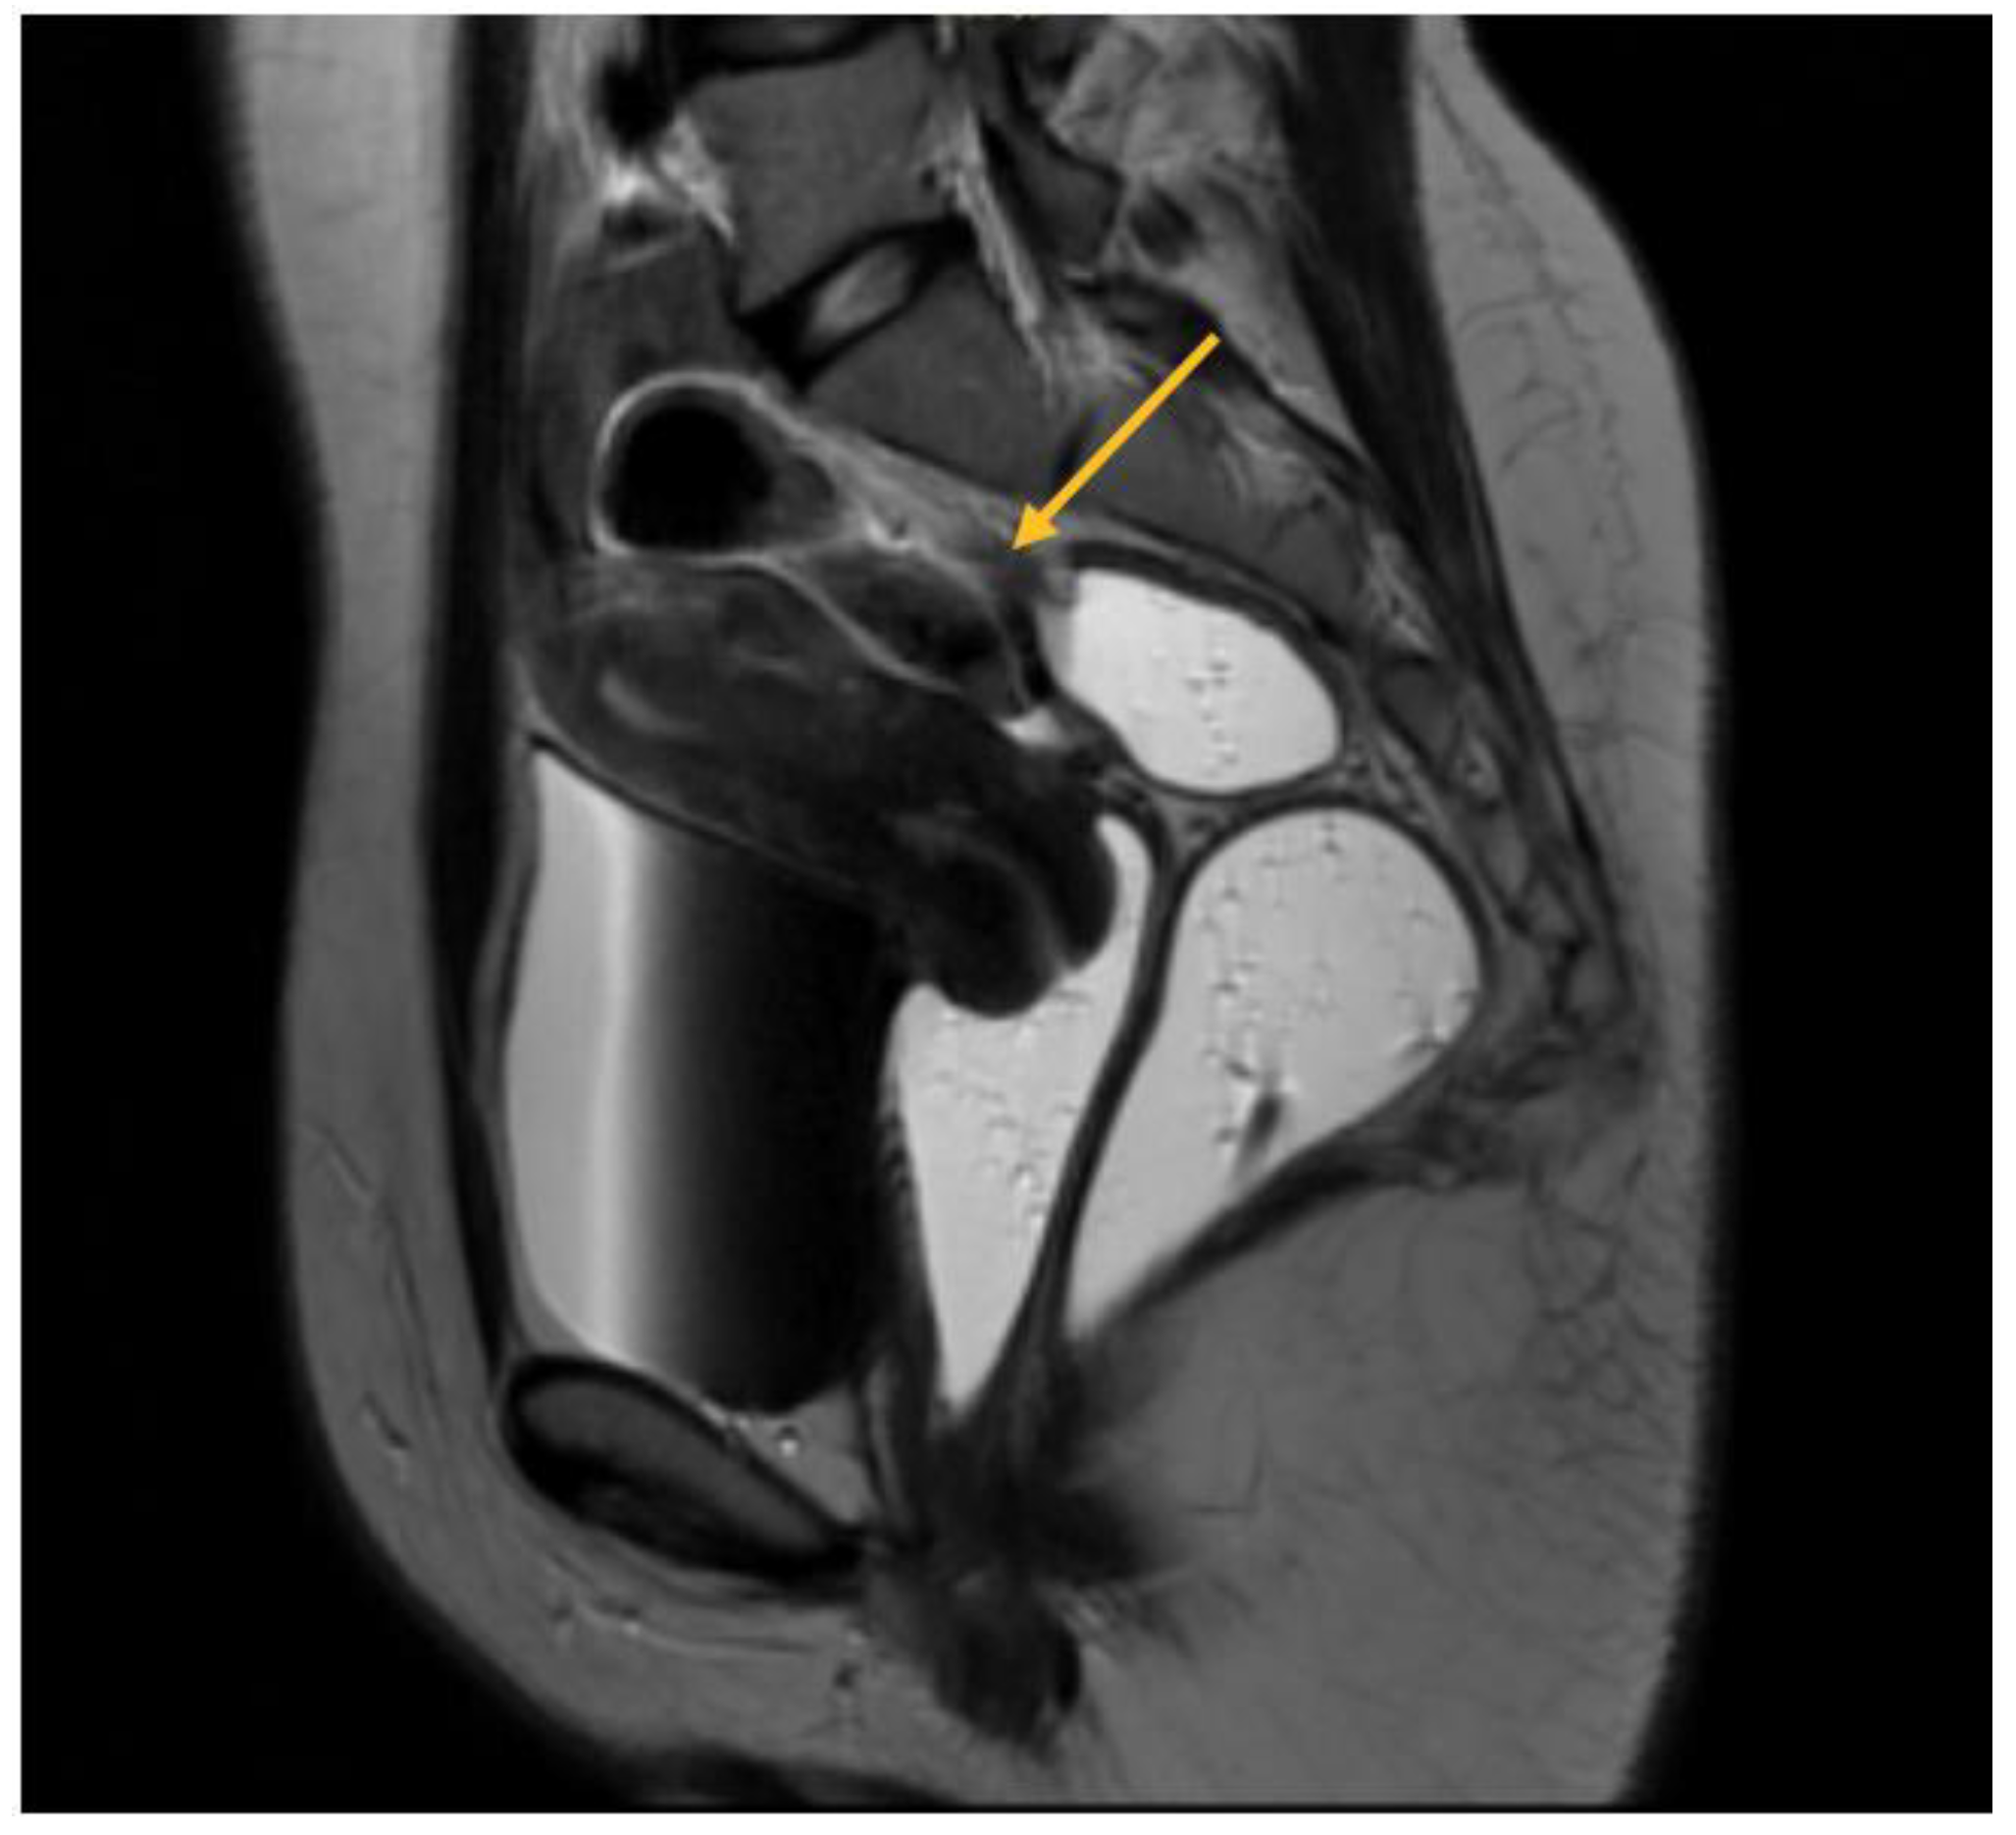

USL endometriosis involvement is usually diagnosed by TVS when assessing the posterior pelvic compartment. USL lesions appear as depicted in Figure 5, as a linear hypoechoic thickening exhibiting either regular or irregular edges [9]. Particularly, we have noticed the nodule appears to have a high-echoic appearance compared to what is commonly described in the relevant literature. However, it is important to highlight that the contour and demarcation of the surrounding structures are clearly discernible.

USL lesions are usually linked to concurrent DIE lesions, the arrow in Figure 5 indicating the presence of a USL nodule connected to a uterine torus DIE lesion. The section indicated by asterisks represents the measurement of the length of the lesions.

Figure 5. TVS aspect of uterine torus and USL endometriosis lesions.